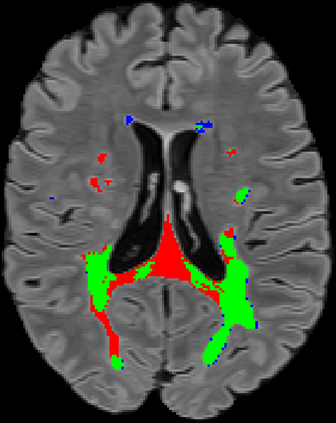

Recently, segmentation methods based on Convolutional Neural Networks (CNNs) showed promising performance in automatic Multiple Sclerosis (MS) lesions segmentation. These techniques have even outperformed human experts in controlled evaluation conditions such as Longitudinal MS Lesion Segmentation Challenge (ISBI Challenge). However state-of-the-art approaches trained to perform well on highly-controlled datasets fail to generalize on clinical data from unseen datasets. Instead of proposing another improvement of the segmentation accuracy, we propose a novel method robust to domain shift and performing well on unseen datasets, called DeepLesionBrain (DLB). This generalization property results from three main contributions. First, DLB is based on a large group of compact 3D CNNs. This spatially distributed strategy ensures a robust prediction despite the risk of generalization failure of some individual networks. Second, DLB includes a new image quality data augmentation to reduce dependency to training data specificity (e.g., acquisition protocol). Finally, to learn a more generalizable representation of MS lesions, we propose a hierarchical specialization learning (HSL). HSL is performed by pre-training a generic network over the whole brain, before using its weights as initialization to locally specialized networks. By this end, DLB learns both generic features extracted at global image level and specific features extracted at local image level. DLB generalization was validated in cross-dataset experiments on MSSEG'16, ISBI challenge, and in-house datasets. During experiments, DLB showed higher segmentation accuracy, better segmentation consistency and greater generalization performance compared to state-of-the-art methods. Therefore, DLB offers a robust framework well-suited for clinical practice.